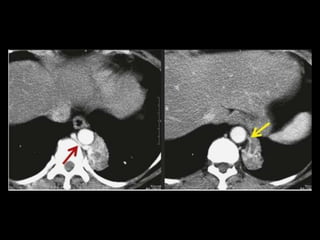

Sequestro pulmonar

Definição: segmento de tecido pulmonar que é

separado da árvore brônquica e recebe seu

suprimento sanguíneo de uma artéria sistêmica;

Dois tipos: intralobar e extralobar;

A maioria dos sequestros são tipo intralobar;

O suprimento vascular em 80-90% dos casos

provêm da artéria aorta descendente;

Complicações: hemoptise e BCP repetição;

Diagnóstico: identificação do vaso anômalo.

Sequestro intralobar com infecções recorrentes

Sequestro pulmonar Definição:segmento de tecido pulmonar que é separado da árvore brônquica e recebe seu suprimento sanguíneo de uma artéria sistêmica; Dois tipos: intralobar e extralobar; A maioria dos sequestros são tipo intralobar; O suprimento vascular em 80-90% dos casos provêm da artéria aorta descendente; Complicações: hemoptise e BCP repetição; Diagnóstico: identificação do vaso anômalo.

Sequestro intralobar cominfecções recorrentes